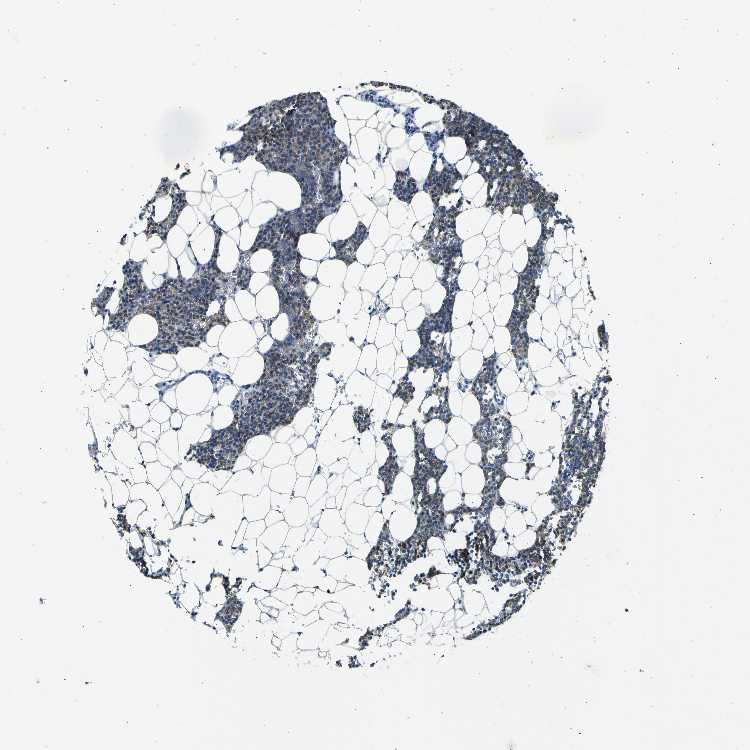

PARATHYROID GLAND - Antibody stainingi

Antibody staining in the annotated cell types in the current human tissue is reported as not detected, low, medium, or high, based on conventional immunohistochemistry profiling in selected tissues. This score is based on the combination of the staining intensity and fraction of stained cells.

Each image is clickable and will lead to virtual microscopy that enables deeper exploration of all samples and also displays staining intensity scores, fraction scores and subcellular localization as well as patient and tissue information for each sample.

Antibody HPA011380

Glandular cells Medium